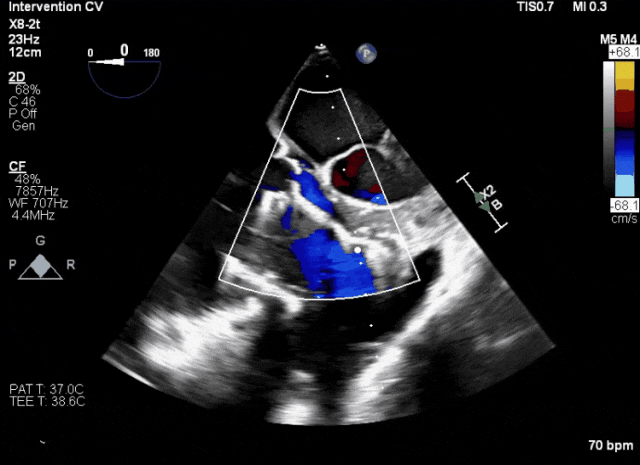

術(shù)前超聲顯示三尖瓣重度反流合并拴系

術(shù)中TEE成像困難,偽影干擾